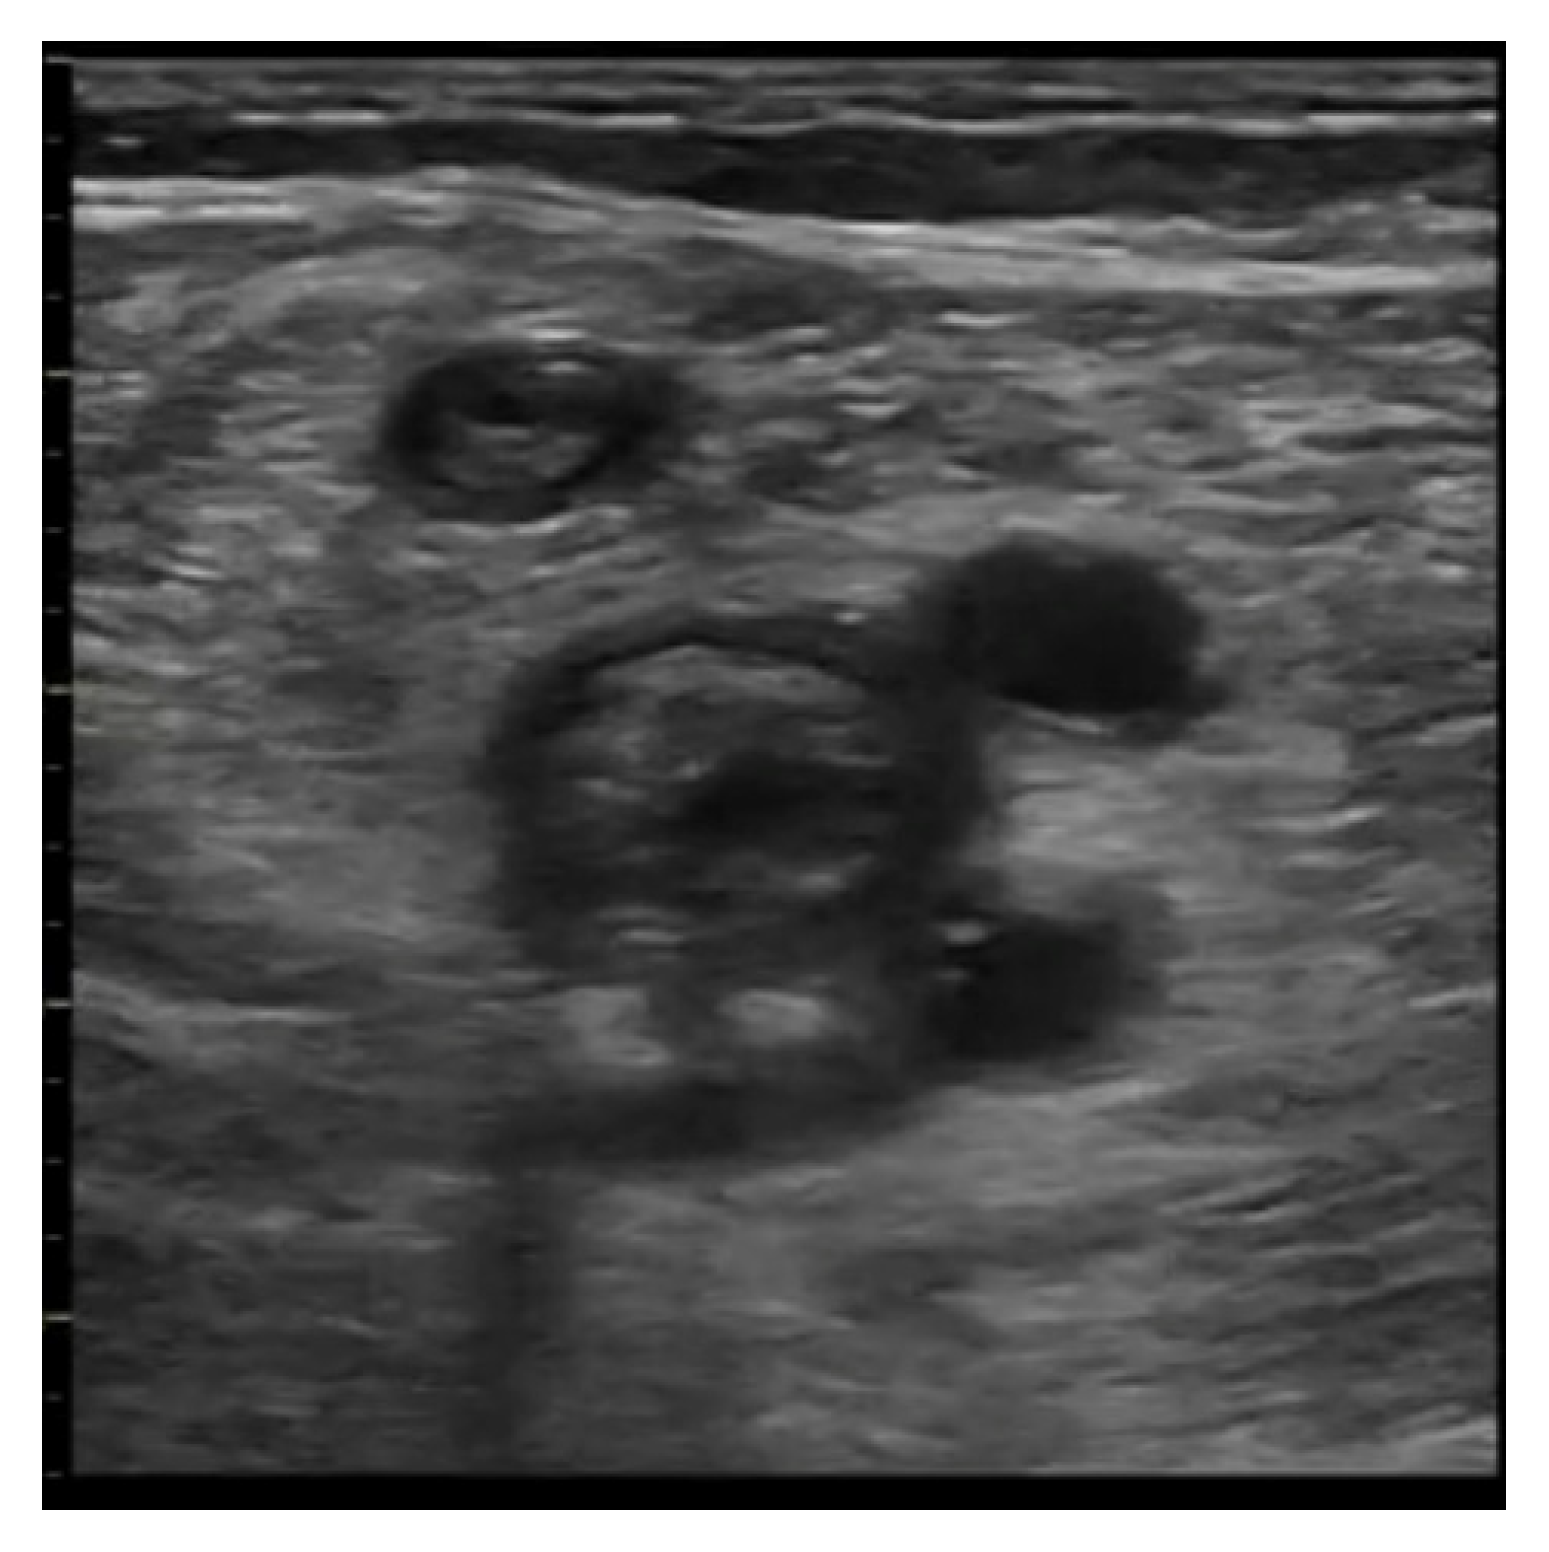

5.2. Imaging

- Acute: the thrombus itself may not be visible. If detected, it is deformable with the force applied on the probe and with a regular surface; it is a distended vein.

- Subacute thrombus: (before six months and after clot formation) intermediate morphological changes that cannot be included in the chronic phase.

- Chronic post-thrombotic change: not compressible nor deformable with an irregular surface; the vein caliber may be normal or reduced.